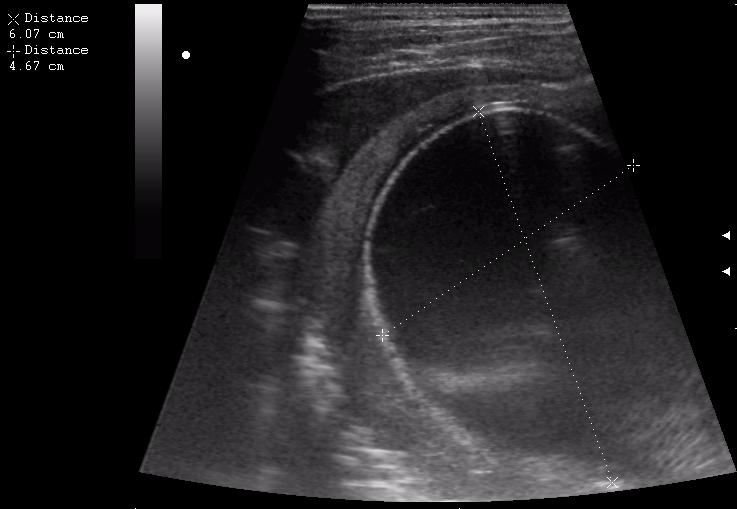

17-летняя девушка с множественными поражениями печени

2.JPG

3.JPG

4.JPG